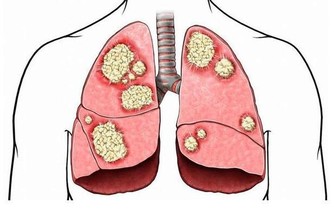

腫瘤研究學者發現,癌細胞並不是一直處於運動狀態,在活躍一段時間後會進入休眠,休眠期過後又再度活躍,興風作浪。 每一個人身上都帶有癌細胞,在人的生命期里,會出現6至10次患癌的機會。 當人被發現有癌症時,意味這個病患是有大量營養缺乏;這可能是由於基因、環境、食物及生活方式等因素造成。 如果能夠讓癌細胞長期處於休眠狀態,便可大大降低患癌的幾率。 一場小型國際研討會,其中有一位目前在美國癌症中心的戴博士以 "IsCancer Curable?" (癌症是否能治癒?)為題,分享了他對癌細胞生長動力學的研究結果。 癌症最令人害怕的就是metastasis(轉移)。 原生癌並不會讓病人死亡,而一旦癌細胞轉移,在其它組織器官內興風作浪就讓病人逐漸(或快速)的走向死亡。但,為什麼有些癌細胞已轉移的病人卻未繼續惡化? 日本曾解剖研究幾十位無病痛往生的 90-103歲老人,發現他們每一位體內都有不少癌細胞。但,為什麼他們的癌細胞沒有造成身體的病痛? 研究發現,癌細胞休眠期越長,病人能存活的時間就越長,甚至不發生令人害怕的轉移。現在醫學界積極的在研究拖延癌細胞休眠期的方法,包括利用藥物和飲食。預防細胞癌化提到幾種天然物,可藉由控制癌細胞內訊息傳導 ( signal transduction ) 的路徑進入休眠期,請大家多吃含有有效成份的食物,讓身體內蠢蠢欲動的癌細胞多多睡覺。 1.姜(抗癌成份是姜油) 2.牛樟芝(抗癌成分是三萜類化合物和 -葡聚糖) 3.綠茶(抗癌成份是兒茶素)